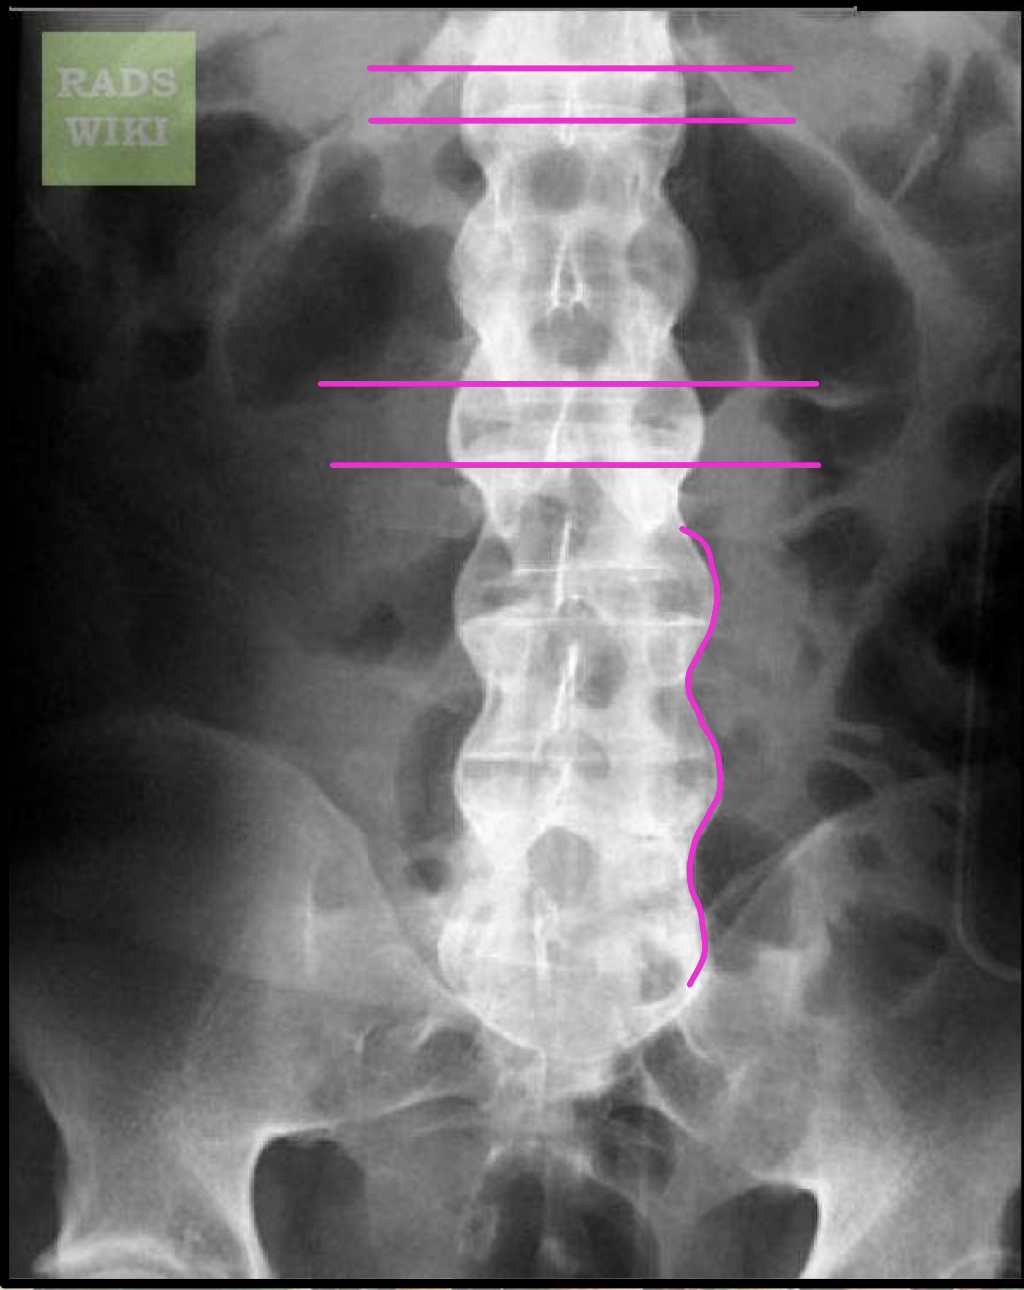

What finding of AS is found in this image

Interspinous ligament ossification (Dagger sign)

Z-joint/facet capsular ossification (Railroad track sign)

Dagger sign + Railroad track sign =

Trolley track sign

Ischial enthesopathy (Whiskering)